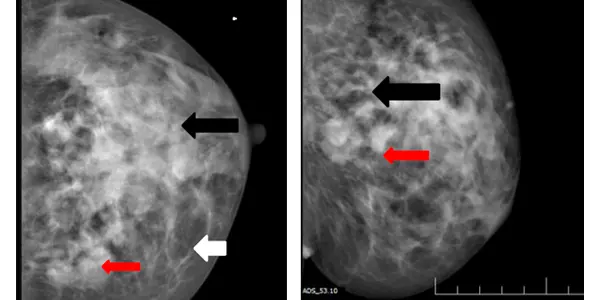

Left breast CC and MLO views

A) & B) Left breast CC and MLO view showing large asymmetric density in upper and central quadrant of left breast (black arrows) with associated interstitial thickening (white arrow) and architectural distortion .Multiple mass like areas seen in the medial and lower quadrant (red arrows) of left breast

A) & B) Large area of abnormality in upper half of left breast with dominant central mass (straight white arrow). Multiple dilated and thickened ducts (straight red arrow)are seen extending from the mass.

C) Multiple lymph nodes (curved white arrow) with thickened cortices in left axilla